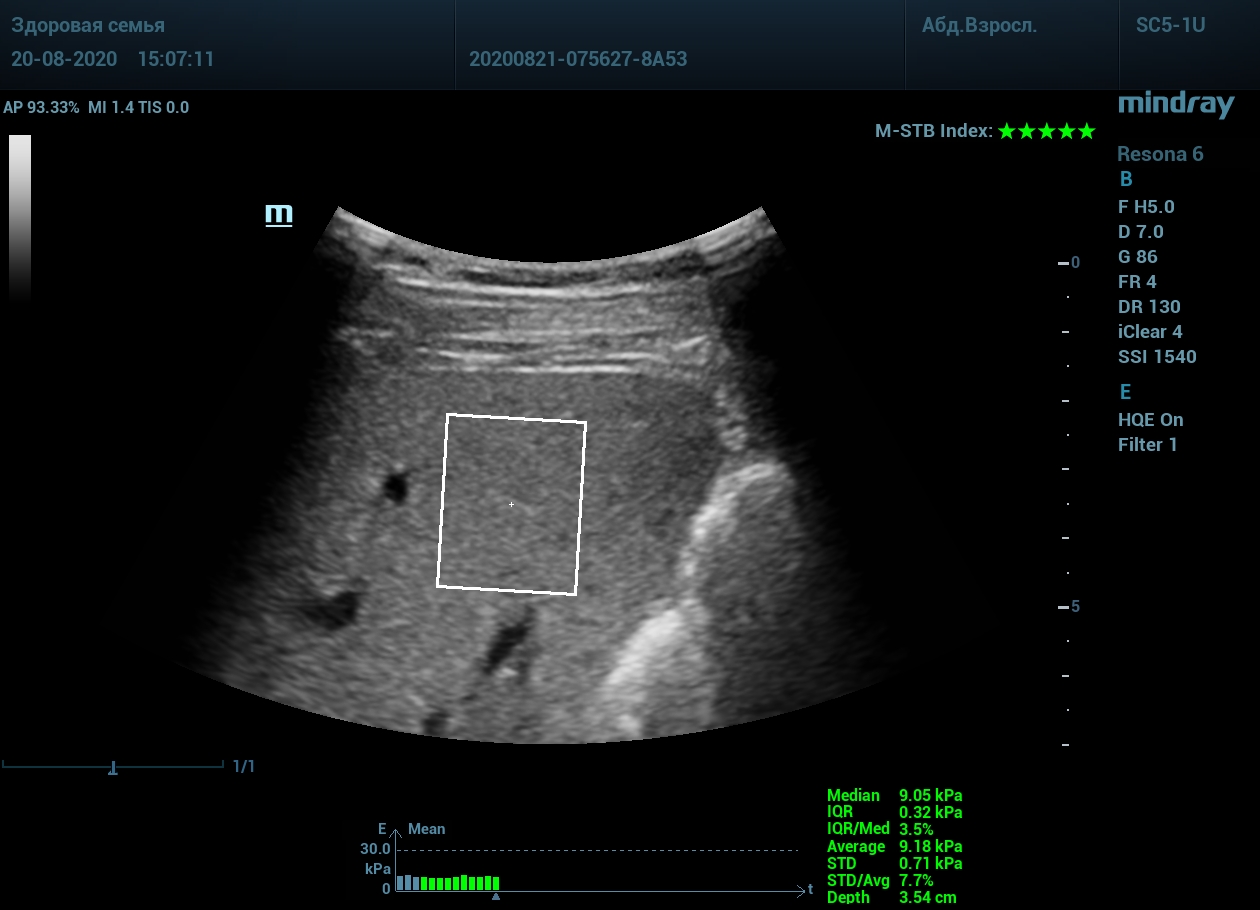

Приводим видео пример: использованы 3 точки доступа печени, каждое значение графика получено прицельным выстрелом HQ Elasto и собрано в единый тренд. В результате анализа 10 значений получен удивительно точный результат - статистический разброс  3.5 % IQR/Med.